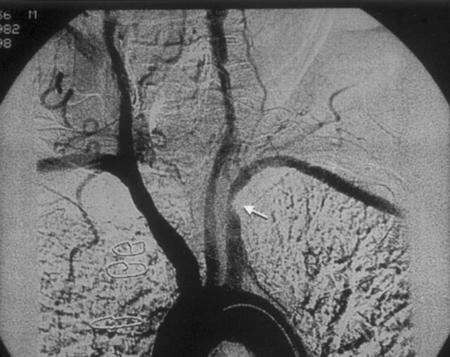

随后的磁共振血管造影显示:左锁骨下动脉狭窄。